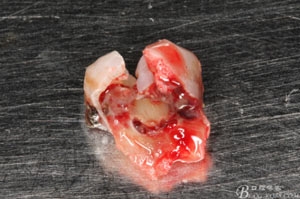

圖8.拔除的37頰側(cè)的牙根完全被壓迫吸收完

圖9.清理牙槽窩過(guò)后。多生牙的牙冠暴露在牙槽窩內(nèi)。